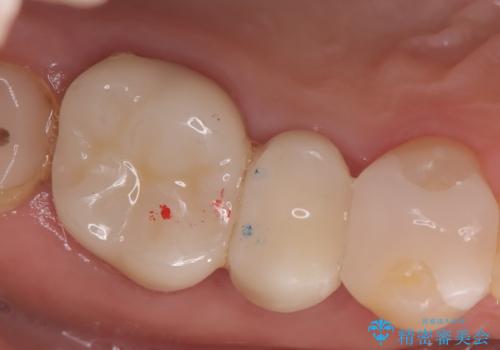

現在入っているインレー・CR裏層を除去し、再度CR裏層・セラミックインレー形成しました。